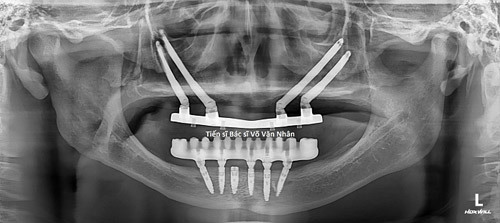

Trả lại nụ cười cho người không răng bẩm sinh

Quá trình phục hồi răng cho các bệnh nhân không răng bẩm sinh gặp nhiều bất lợi vì bệnh nhân không có xương hàm để lưu giữ và nâng đỡ hàm giả. Đã có bác sĩ Việt phẫu thuật cấy ghép răng thành công cho những trường hợp này.